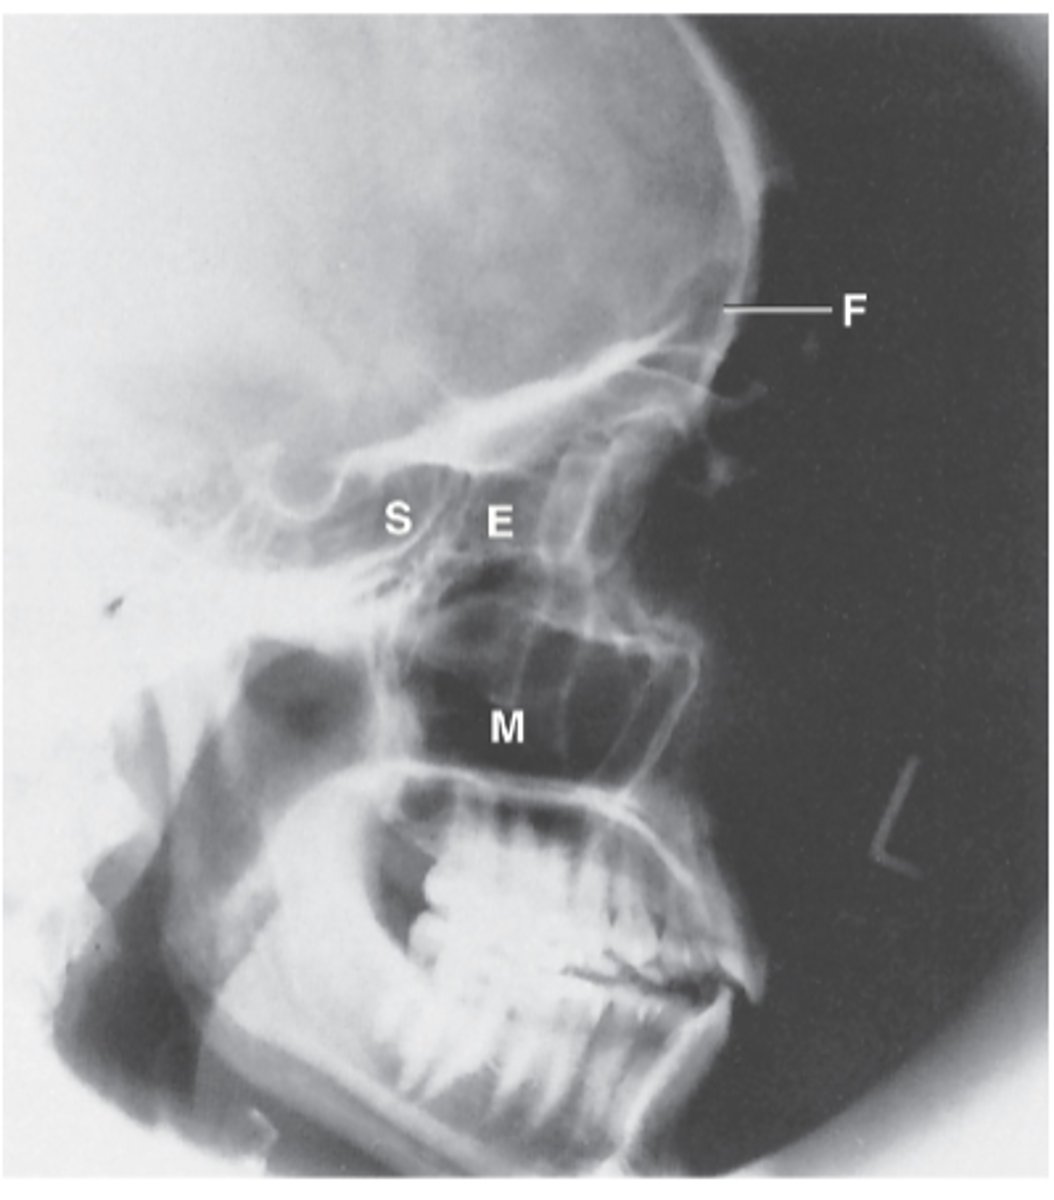

Ethmoid Sinus

E

Sphenoid sinus

S

Maxillary sinus

M

Frontal sinus

F

PA axial (Caldwell Method)

What projection is this?

CR exits the nasion & 15 degree caudal angle

What is the CR for PA axial (Caldwell Method)?

OML perpendicular to IR

What line should be perpendicular to the IR for a PA axial (Caldwell Method)?

Interpupillary line (IPL)

What line is parallel to the IR for a PA axial (Caldwell Method)?

Frontal and Ethmoid

What sinuses are clearly demonstrated on the PA axial (Caldwell Method)?

Lower 1/3 of orbits

Where are the petrous ridges located in a PA axial (Caldwell Method) radiograph?